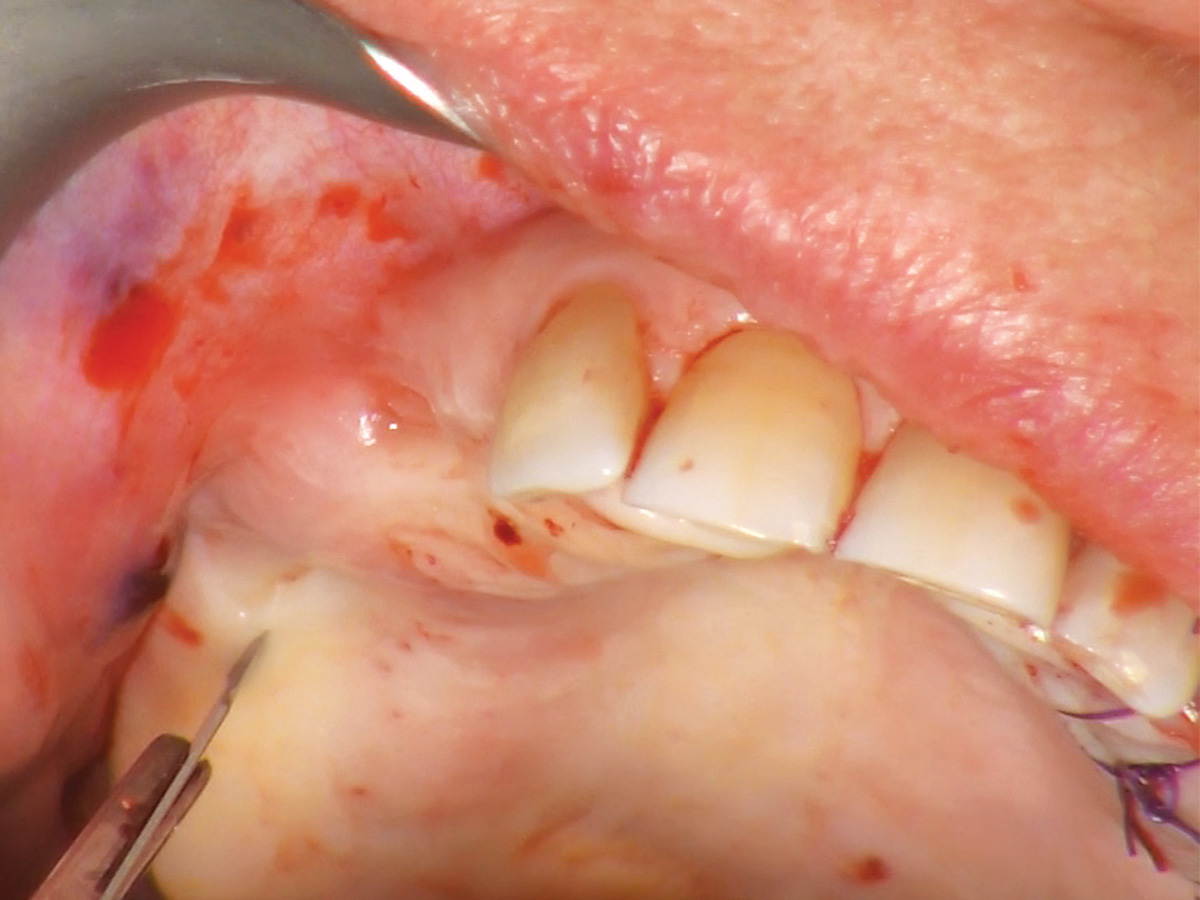

Abbildung 7

Einsetzen der Gingivaformer nach vier Monaten.

Abbildung 8

Wundverschluss, Okklusalansicht.